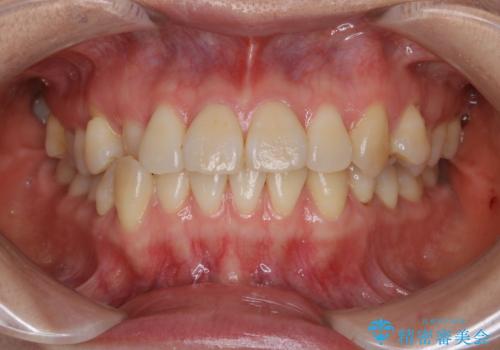

上下裏側矯正 フルリンガルによる上下前歯前突の歯列矯正

- 20代女性

- 舌側矯正装置

- 口元を改善するため、上下左右4本の第1小臼歯を抜歯し、前歯を後方に牽引する計画としました。